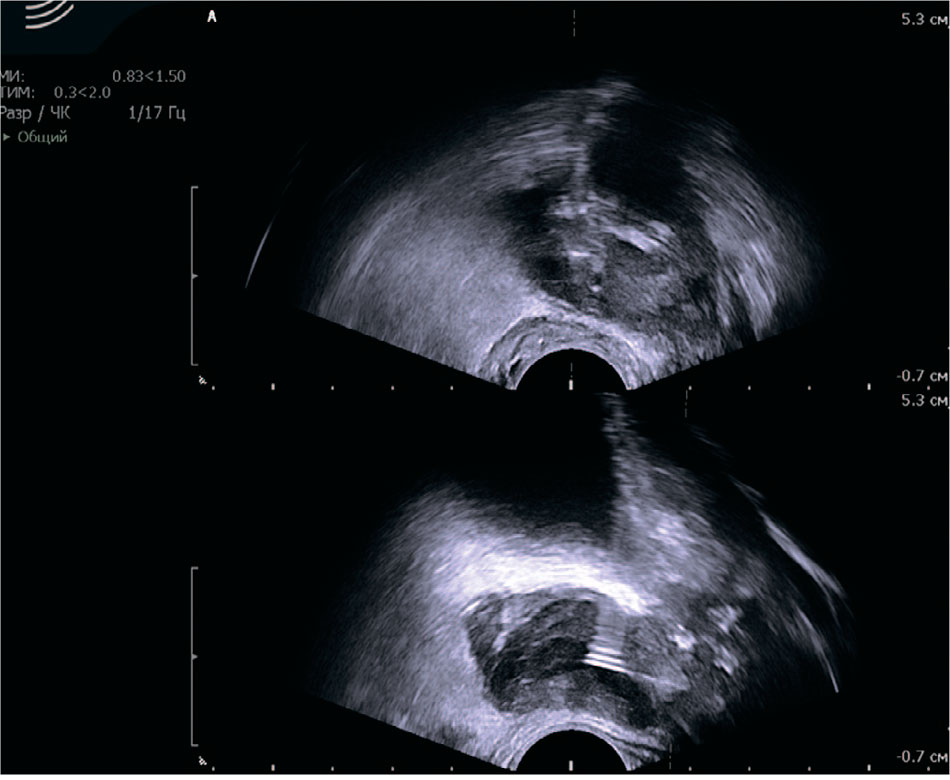

Пациенту было выполнено трансперинеальное пункционное дренирование абсцессов правой и левой долей предстательной железы с установкой дренажей типа Pig tail №10. Получено 4 мл и 5 мл гнойно-геморрагического содержимого из левой и правой долей предстательной железы соответственно (рис. 2, 3). При бактериологическом исследовании выявлен рост Klebsiella pneumoniae 107 КОЕ/мл с выраженной антибиотикорезистентностью. В послеоперационном периоде проводилась антибактериальная терапия согласно бактериологическому посеву пунктата. Отделяемое по дренажам за все время стояния последних было скудным, а при контрольном ТРУЗИ на 3-и и 8-е сутки наблюдалась положительная динамика. Дренажи удалены на 9-е сутки после операции. На фоне проведенного лечения отмечалась нормализация температуры тела, исчезновение дизурических симптомов, снижение уровня С-реактивного белка (СРБ) со 105 до 4 мг/л, уровня креатинина с 309 до 232 мкмоль/л и уровня мочевины с 12 до 8,1 ммоль/л. Пациент был выписан в удовлетворительном состоянии с назначением 4-недельного курса антибактериальной и антимикробной терапии для продолжения лечения в амбулаторных условиях.

Рис. 2. Ультразвуковая картина пункционного дренирования абсцессов предстательной железы

Fig. 2. Ultrasound findings of percutaneous drainage of prostate abscesses